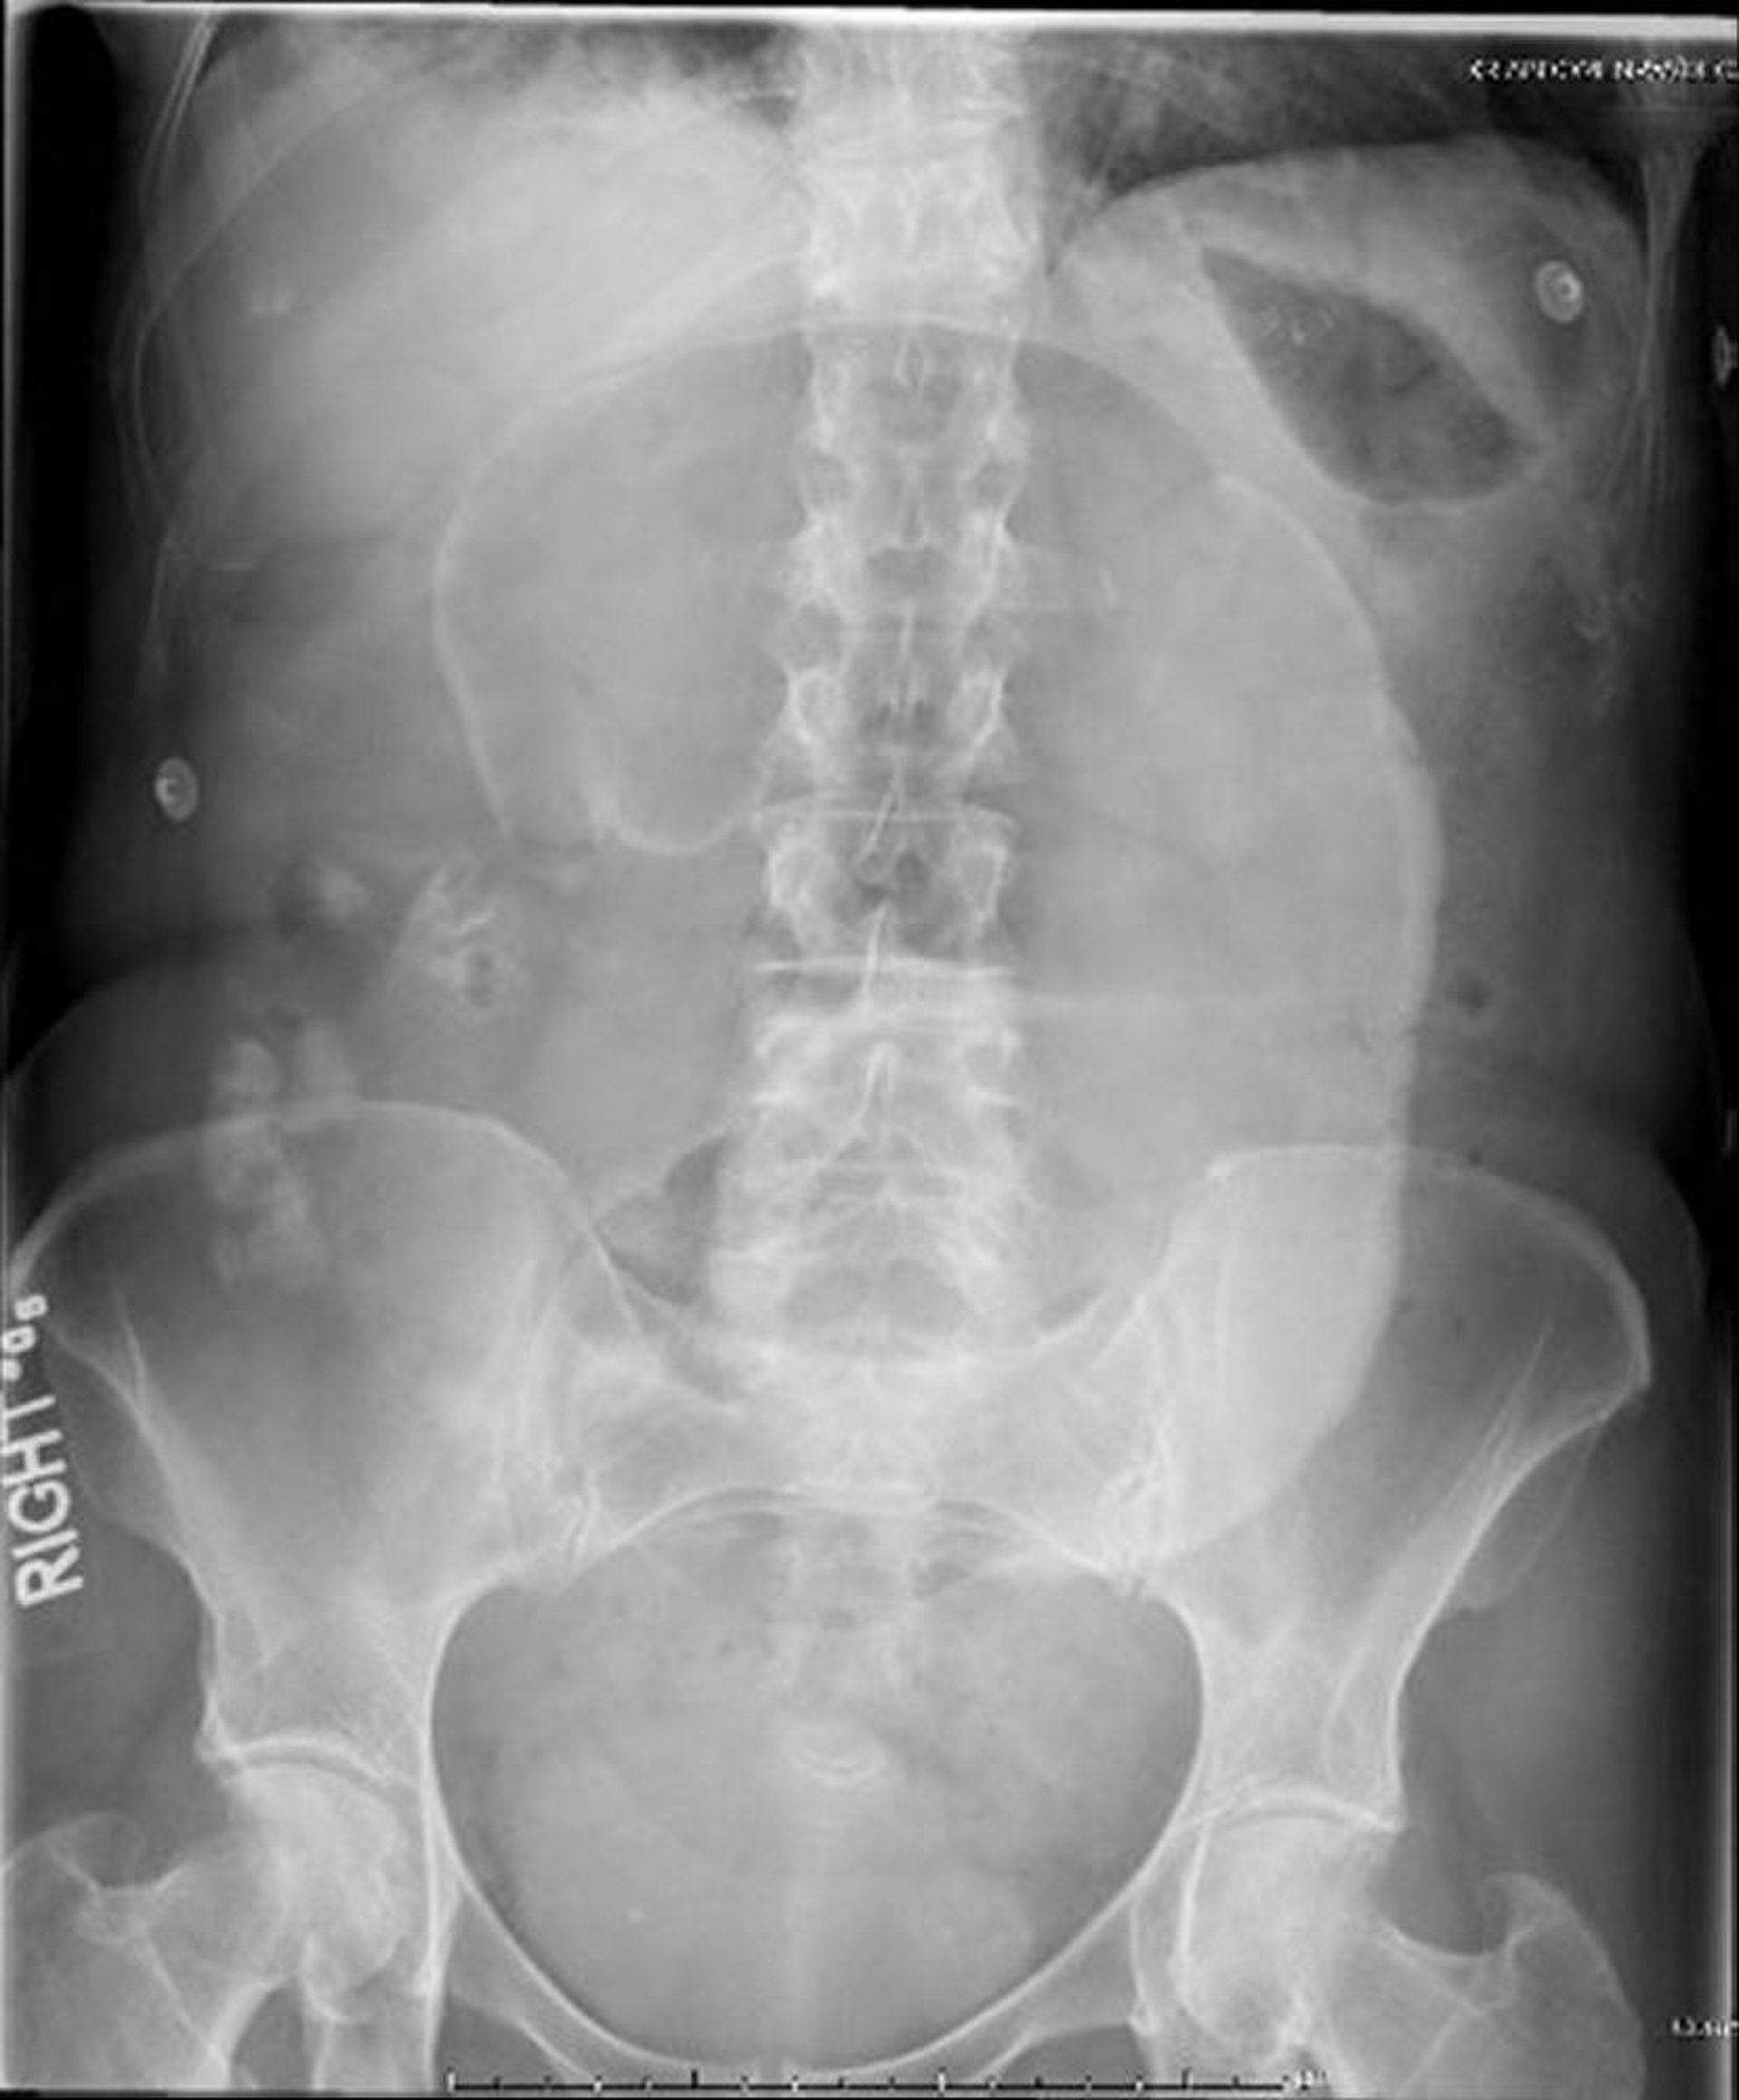

Vólvulo cecal (radiografía de abdomen)

En esta radiografía abdominal, el ciego presenta torsión alrededor de su mesenterio, lo que causa la proyección hacia el cuadrante superior izquierdo de un asa dilatada (signo del "grano de café").

Image provided by Parswa Ansari, MD.